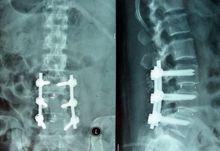

三,傳統手術,後兩種是根治的辦法,根據患者的病情採取不同的治療方法!

退變腰椎圖示保守治療:包括臥床休息、按摩,藥物、牽引、推拿、針灸封閉等法,適合於初發或病情較輕的病例。其療法目的促使突出部位回納,改善局部血循環, 增大椎間隙以減輕對神經根的壓迫刺激, 消除因突出物壓迫神經引起的水腫、炎症,暫時緩解了症狀的,但此療法基本上是不能徹底消除和回納突出的椎間盤。微創手術治療:進入二十一世紀,國內外專家學者對解剖學、生物化學、生物力學及影像學等方面詳盡研究的基礎上,微創介入治療技術取得了突飛猛進的發展。與傳統手術方法相比,微創手術治療技術具有創傷小、恢復快、不破壞椎管內正常結果及不影響脊柱生物力學穩定性等優點。如:經皮雷射椎間盤汽化減壓術、臭氧微創介入治療術、膠原酶生物溶解術等。微創手術治療已成為現代醫學發展的趨勢。

微創介入治療椎間盤突出的原理:機器引導及微小几乎無創傷的情況下,通過細小的導管或穿刺針準確直接作用於突出部位,通過物理的因素,消融或溶解突出物,使突出物回縮或消失,解除了對神經的壓迫,達到和開刀治療同樣的療效。但是具體能不能做,需要結合病情和片子綜合分析!